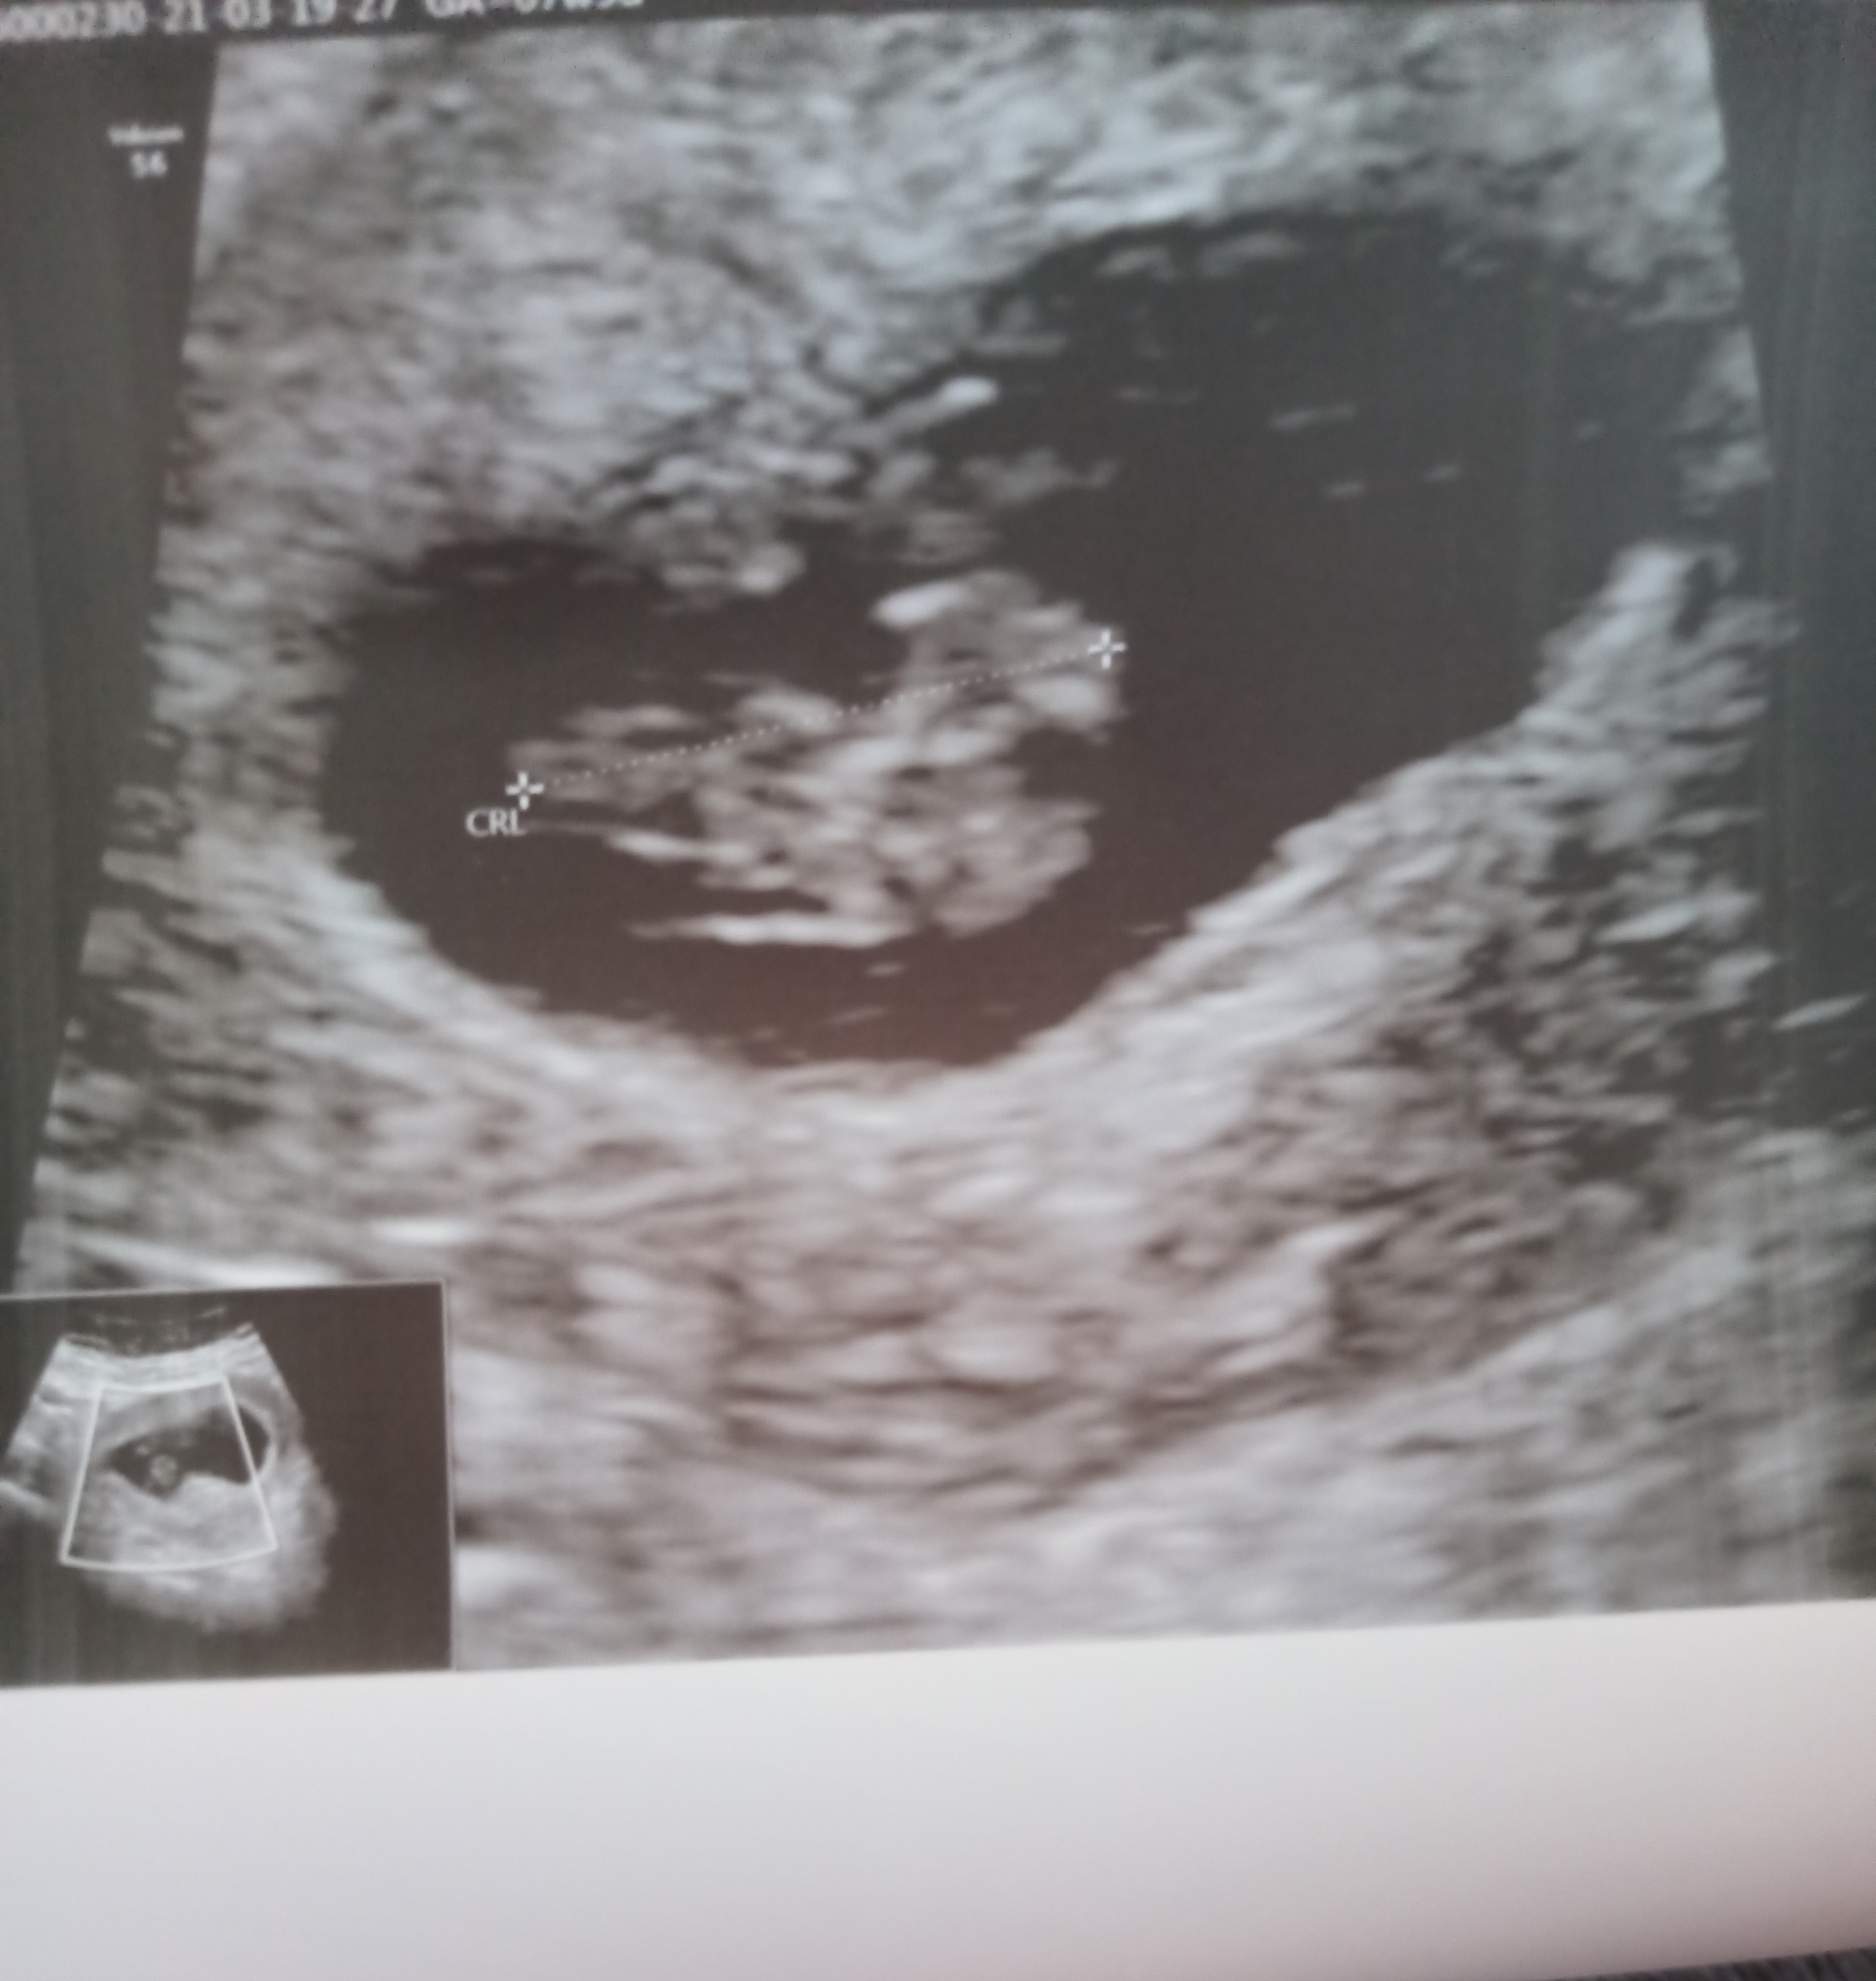

Serduszko 164 uderzenia na minutę ,”gadzina” ma już 1.7cm, wiek ciąży 8t1d.

Co prawda trafiłam na strasznego buraka, który na moje pytanie czy wszystko wygląda ok odpowiedział tylko - "ja tylko stwierdzam ciąże, ciąża żywa " ;) więc więcej pytań już nie miałam :d

• IMG_20210319_171123.jpg

IMG_20210319_171123.jpg

1,4 MB · Wyświetleń: 93